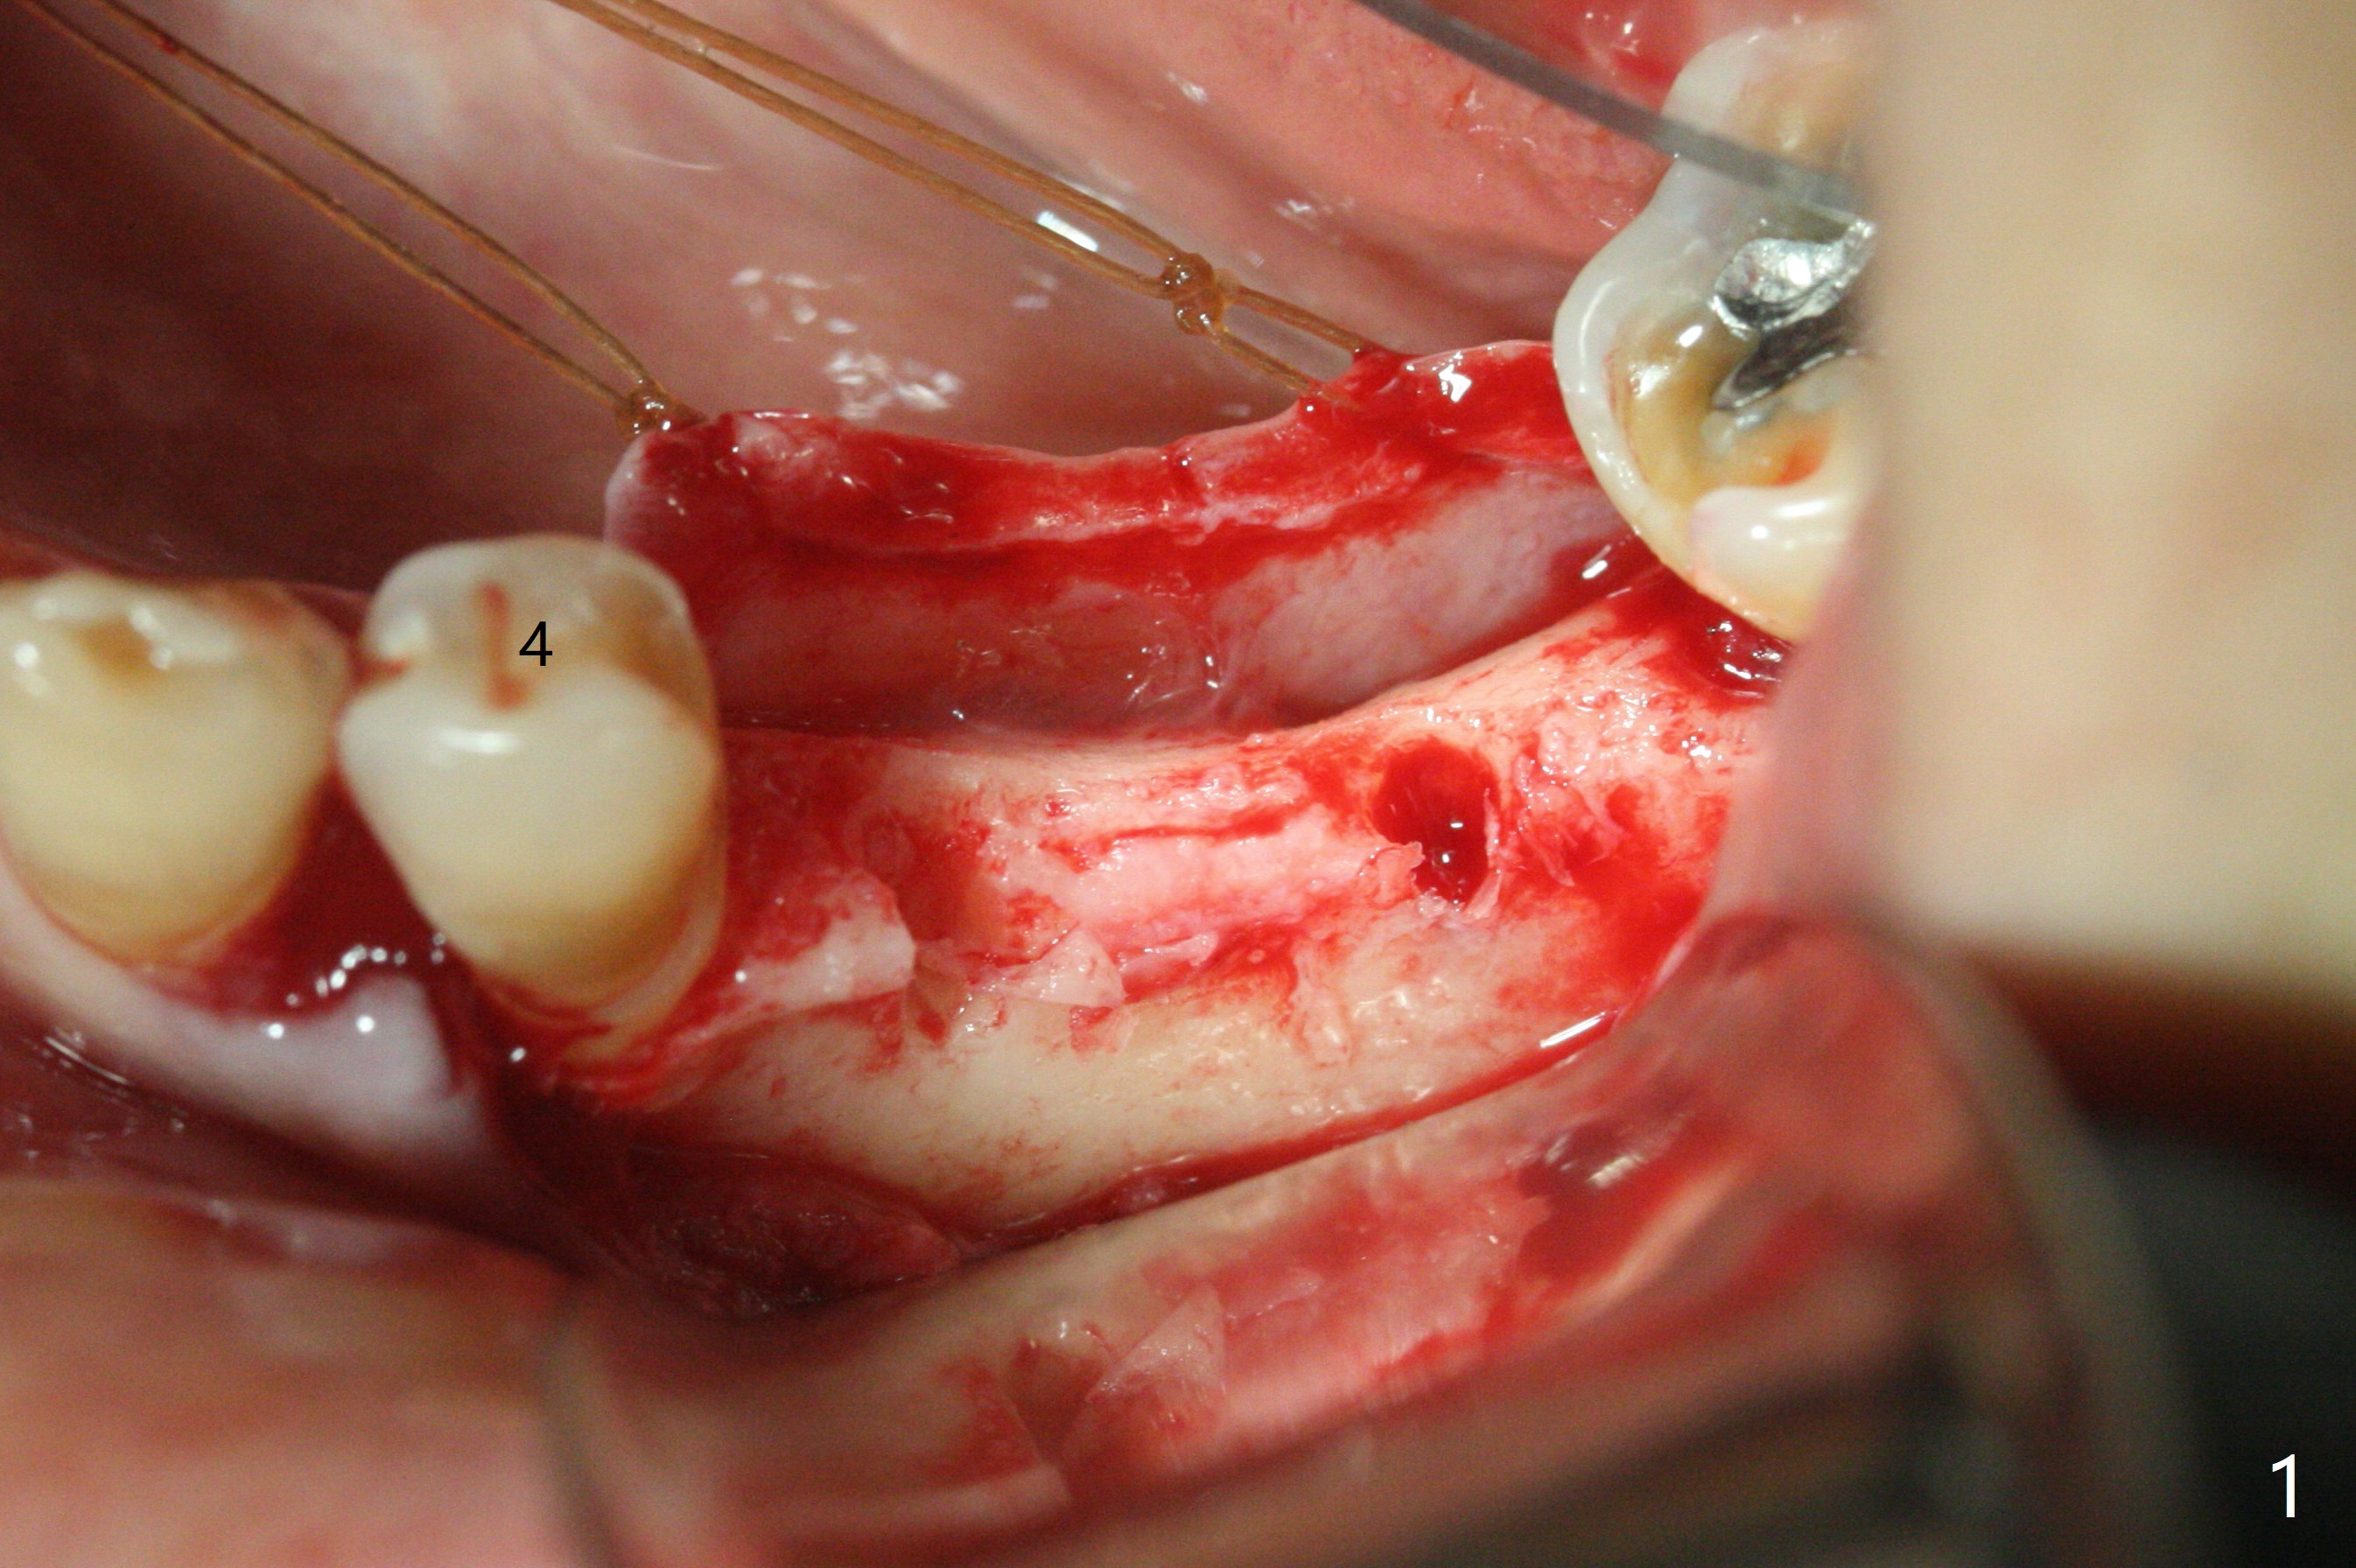

左下5,6切开,使用导板钻洞,都偏向颊侧(图一),好像牙槽嵴太狭窄,不适合做劈开术,然后改为自由手,使用Lindermann(侧方)钻头将钻洞往舌侧迁移,完成一段式植体初步钻洞(图二)以及植体植入(图三:2.5毫米(直径),根据近远中距离,植体不显得太窄)。尽管下齿槽神经阻断麻醉(开始浸润麻醉),病人疼痛明显,不敢下沉远中植体太多(图四:>),放置粘性骨块(图五,六:*)和PRF膜。缝合后,调整基台以及对合牙高度(图六: <),最后放置牙周敷料。由于植骨,术后15天植体周围形成致密的牙龈带(图七:*(gingival band))。术后一个月安置临时连体牙冠,没有任何咬合接触,主要目的防止7近中倾斜。术后三个半月临时牙冠被吞入,右侧托牙也不见了,局部牙龈健康,塞入2-0 gingival retraction cord(增加5基台长度(今后牙冠固位),图八 (>:植体螺丝刀终止地方)),取模。永久性牙冠边缘不重要,由实验室决定。清除残余粘固剂也不是很困难(图九)。